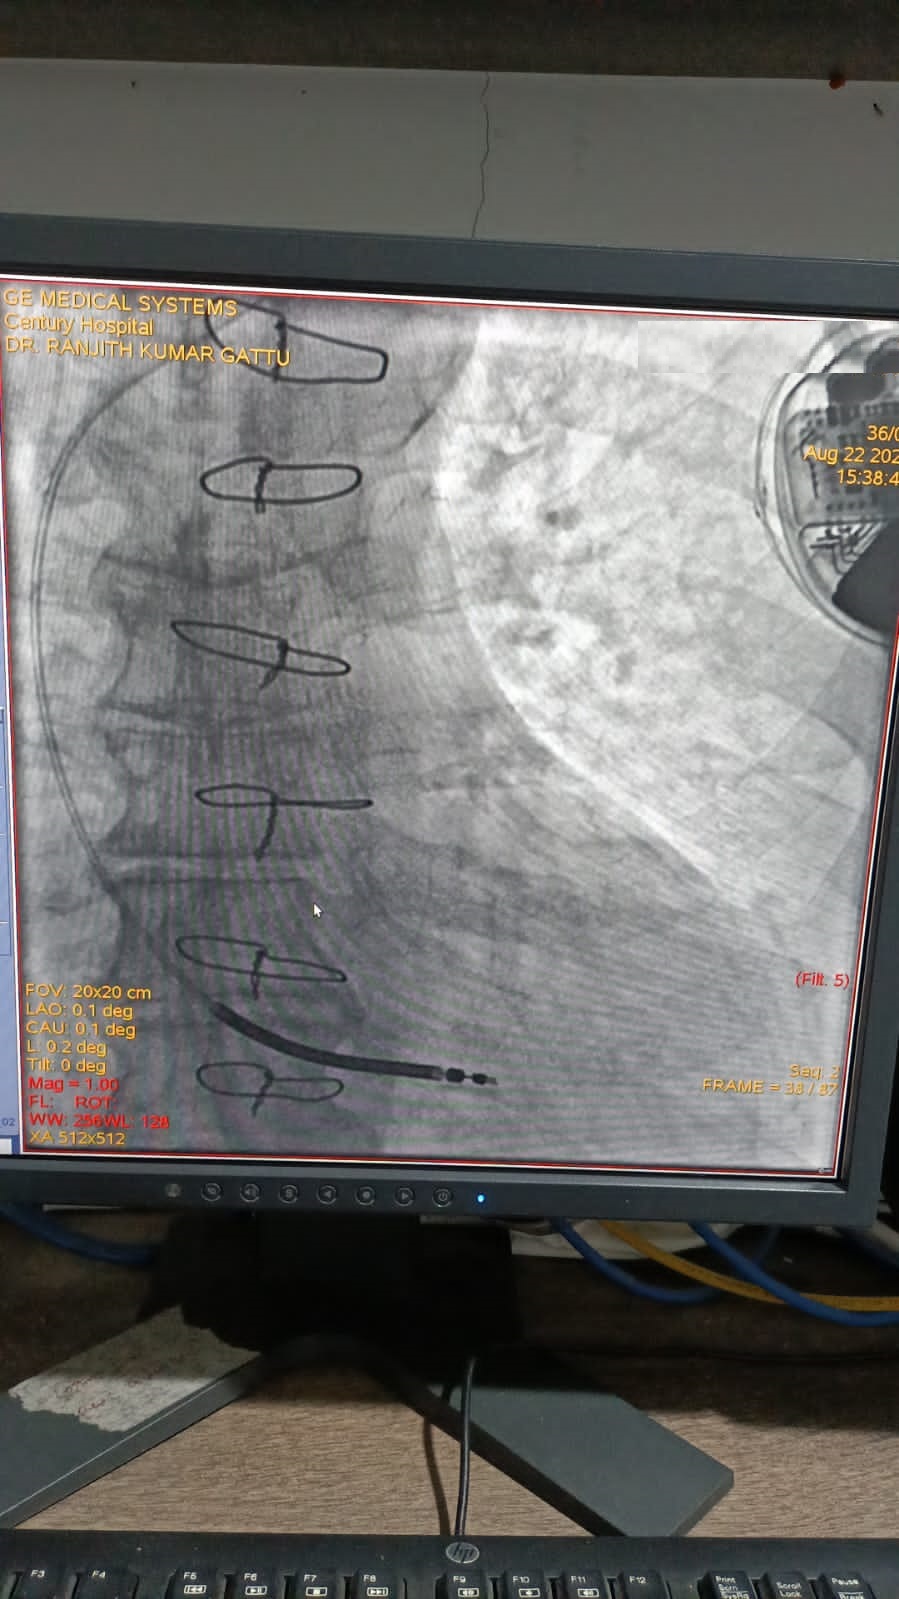

Catheter ablation of arrhythmias

Right Coronary Diseased Artery